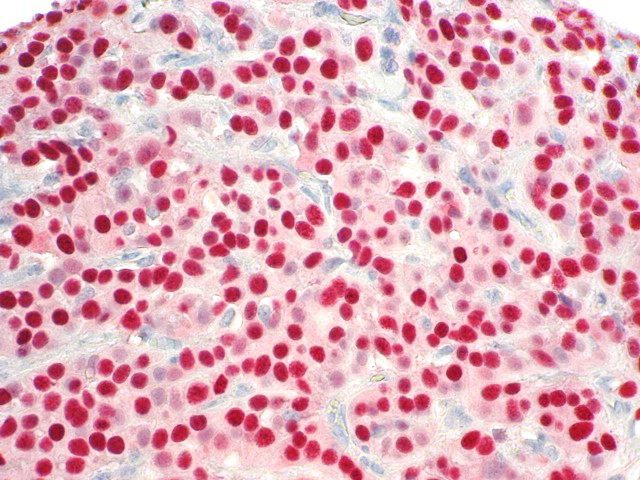

It is the ICU physician who is most likely to witness one of the deadliest manifestations of the abnormal immunological response, the cytokine storm syndrome (CSS). This response is also referred to by some as the cytokine release syndrome (CRS). CSS is characterized by continuous activation and expansion of macrophage and lymphocyte populations, which secrete large amounts of cytokines, causing the cytokine storm. This massive cytokine release is akin to hemophagocytic lymphohistiocytosis (HLH) disease, a syndrome characterized by initial unchecked and persistent activation of cytotoxic T lymphocytes and NK cells.

Clinical and laboratory manifestations of HLH include fever, enlarged liver and/or spleen, neurologic dysfunction, coagulopathy, liver dysfunction, cytopenias (i.e., low levels of erythrocytes, leukocytes, and/or platelets), hypertriglyceridemia, hyperferritinemia, hemophagocytosis, and eventually diminished NK cell activity as the immune system becomes progressively paralyzed. HLH can be familial (primary HLH) or secondary to another disease process (sHLH), such as rheumatic disease, in which it is referred to as macrophage activation syndrome (MAS, characterized by elevated ferritin).